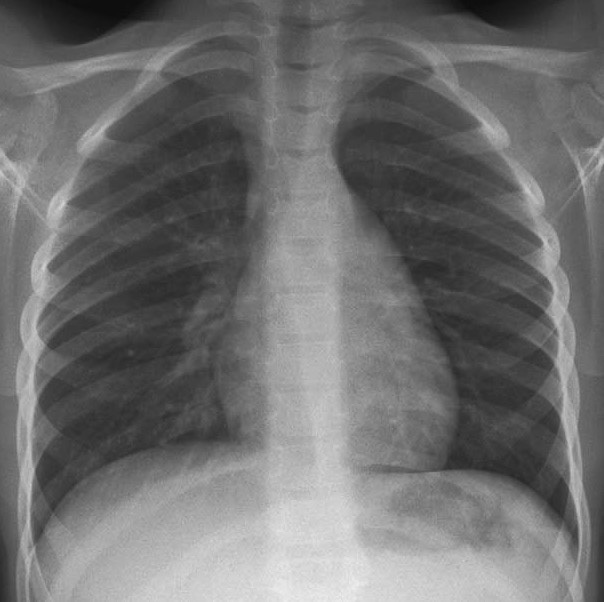

Vous réalisez une radiographie pulmonaire de face.

Figure 1.

Question 3 - La radiographie pulmonaire met en évidence (une ou plusieurs réponses exactes) :

Visibles au niveau du lobe supérieur gauche.